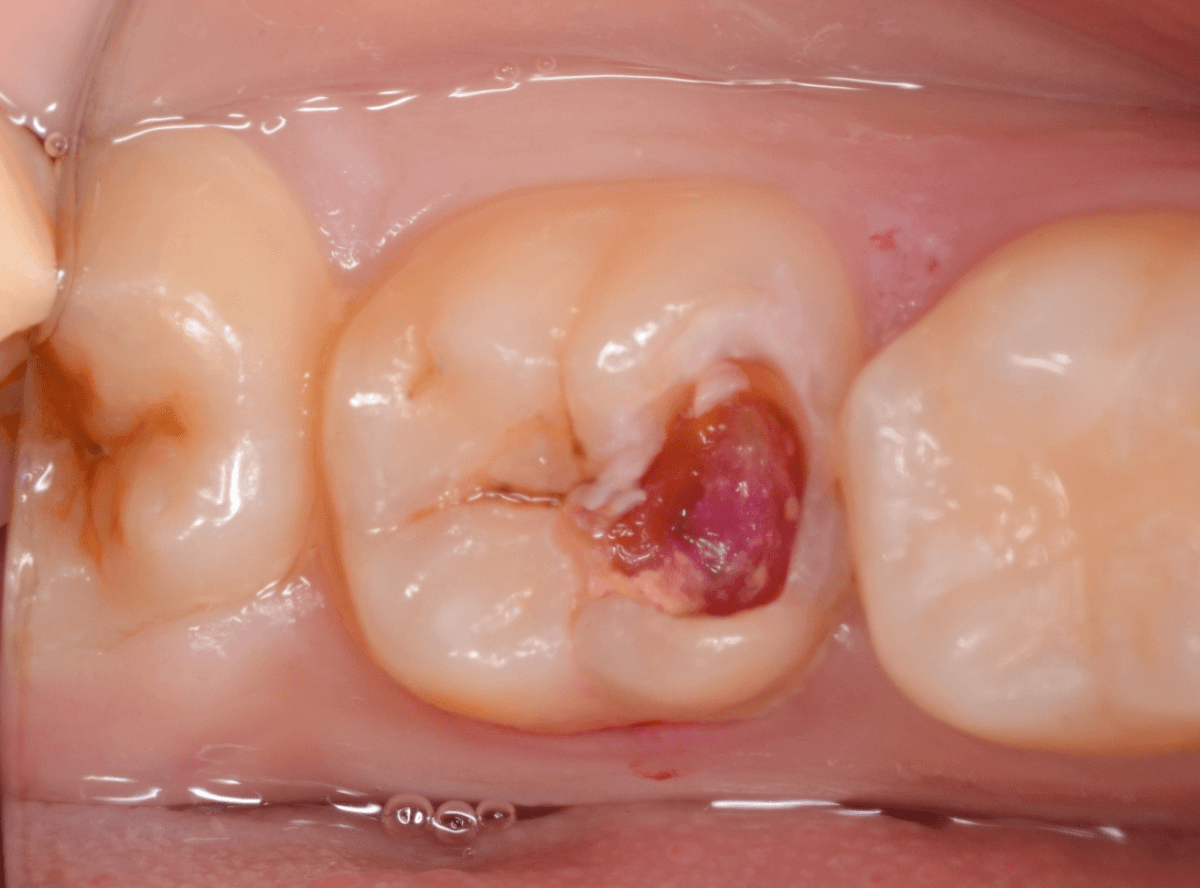

インレーを除去して、治療を開始します。

ある程度、虫歯を除去したところで、う蝕検知液で確認します。

赤い部分が虫歯です。

やはり、レントゲン写真で確認した部分が深めの虫歯になっていたようです。

全ての虫歯を除去しました。

お薬をつめて痛みやしみが出ないか、しばらく経過観察しますが、おそらく大丈夫でしょう。

症状が出る前に、検診に来ていただいたことで最小限の治療で済みました。